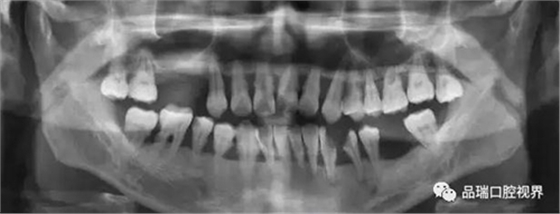

刷牙出血、牙齦紅腫、疼痛,這種情況幾乎人人都有過。在疲勞、生活不規(guī)律,刷牙潦草時更容易出現(xiàn)。很多朋友以為牙齦出血是因為缺乏某種維生素。其實,雖然長期嚴(yán)重缺乏維生素C確實會導(dǎo)致牙齦出血紅腫,但除非一連兩三個月都不吃蔬菜水果牛奶等含有維生素C的食物,否則,除了極少數(shù)人是由于血液病等全身疾病,絕大多數(shù)牙齦出血都是牙齦炎的表現(xiàn)。牙齦出血,原因多為牙齦炎或牙周炎。

牙周炎是一種漸進性的疾病——就是說它并不會像普通感冒一樣,不管治不治療,只要不繼發(fā)感染,一周左右都會好。如果不對炎癥和口腔的刺激因素進行控制,牙齦炎會進一步發(fā)展為牙周炎,這就不再是僅限于軟組織的炎癥,而是會累及牙槽骨,當(dāng)骨質(zhì)緩慢喪失,牙齒就失去了支撐,開始松動,最終導(dǎo)致牙齒脫落。